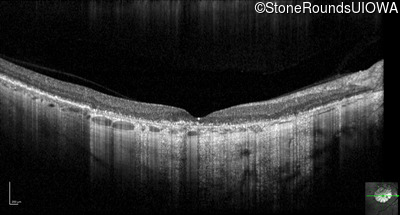

Optical Coherence Tomography - Right - 20/63

Exemplar / OCT Stack